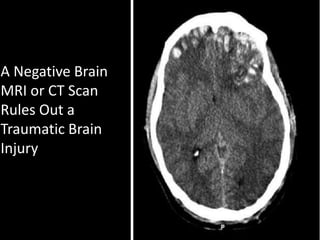

A Negative Brain

MRI or CT Scan

Rules Out a

Traumatic Brain

Injury

In Mild TBI, Most Damage to Brain is Microscopic

& Rarely Shows Up on MRI or CT ScanFACT

Normal Axons

Are Less Than 5

Microns – Less

Than Size

Threshold for

Detection by

MRI or CT

Diffuse Shearing of Billions of Axon Occurs

in Traumatic Brain InjuryFACT

Billions of Axons Can Be Damaged Without

Detection By MRI or CT Through ShearingFACT